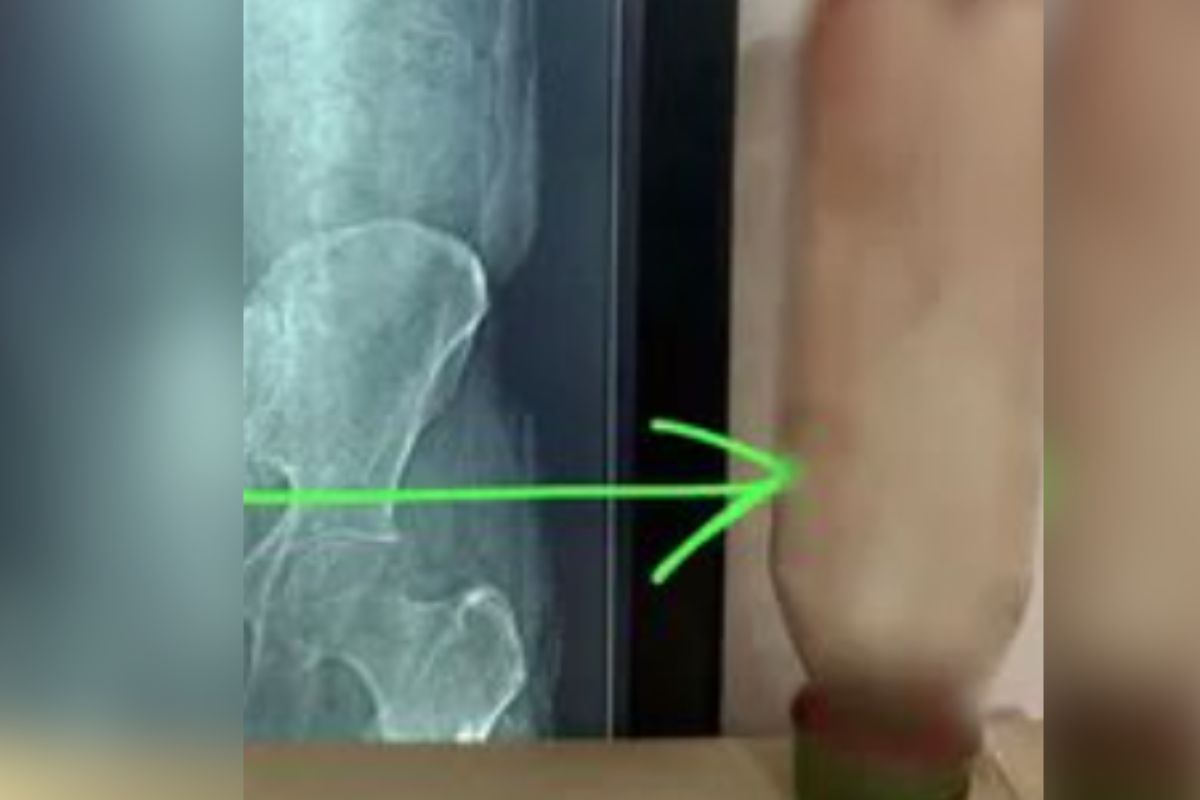

मिली जानकारी के अनुसार, पीड़ित ने खुद ही बोतल को मलद्वार के रास्ते अंदर प्रवेश कराया था। हालांकि, बोतल के फंस जाने के बाद उसे गंभीर दर्द और सांस लेने में तकलीफ होने लगी। UP News जब दर्द असहनीय हो गया, तो उसे तत्काल अस्पताल ले जाया गया। डॉक्टरों ने एक्स-रे और अन्य जांच की, जिसमें मलाशय के भीतर बोतल स्पष्ट दिखाई दी।मामले की गंभीरता को देखते हुए डॉक्टरों की एक टीम ने तुरंत सर्जरी का निर्णय लिया। सर्जरी के माध्यम से लगभग 36 घंटे बाद बोतल को शरीर से सफलतापूर्वक बाहर निकाला गया। डॉक्टरों के अनुसार, यह कोई सामान्य दुर्घटना नहीं, बल्कि एक साइको-सेक्सुअल डिसऑर्डर’ (Psycho-sexual Disorder) का मामला है।